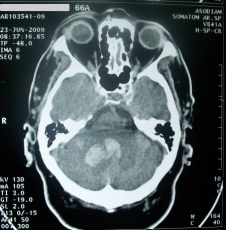

![[Img #51121]](upload/img/periodico/img_51121.jpg)

En la foto, de izquierda a dcha, los doctores Atocha Romero, Daniel Rueda y Gijs Jochems. (Foto: Promega)